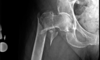

Extracapsular NOF

Subcapital fracture (intracapsular)